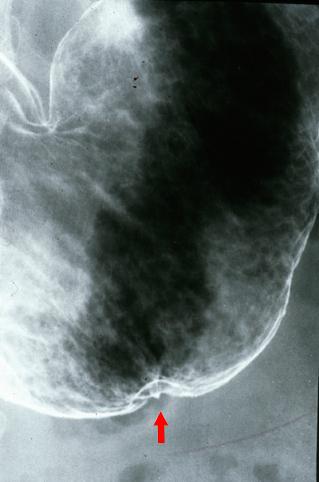

疾病(病理主体)的分类恶性上皮性肿瘤/腺癌

部位(按器官分)胃(部位)/胃角

检查方法X线

肿瘤的肉眼分类0型(表在型)/IIa型(IIa+IIc)

肿瘤最大直径20~24

肿瘤的深度sm